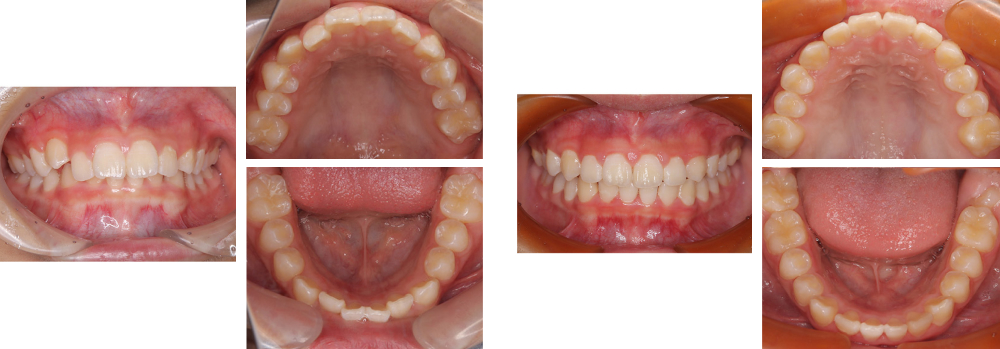

小児矯正

術前

術後

| 治療内容 | 叢生に対して床矯正を使用し治療を行った |

|---|---|

| 治療期間・回数 | 20カ月間・19回(動的治療まで) |

| 費用 ※自由診療となります |

矯正検査①:33,000円 床装置(ネジあり):77,000円 ×2 床装置(ネジなし):55,000円 ×2 |